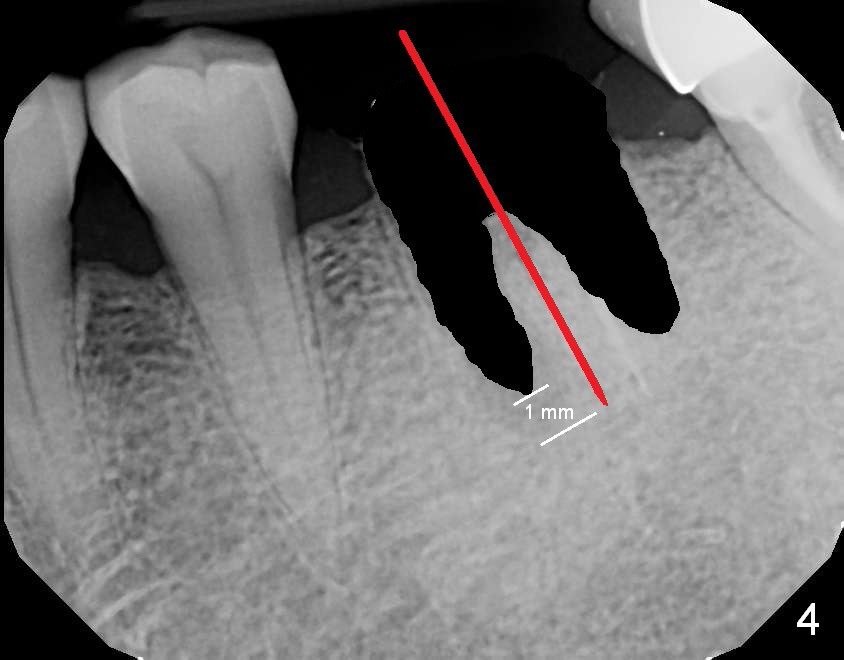

A 69-year-old man has pain in the tooth #19 (Fig.1). When a rubber dam clamp is placed for retreatment, the crown falls out (Fig2). Due to short clinical crown, the tooth is deemed non-salvageable. Fig.3 is an illustration after extraction. It seems that the septum is wide at the base. Measure socket depth. An osteotomy will be 1 mm longer than the socket depth (Fig.4). The osteotomy is initiated in the middle of the septum 14 mm deep. Insert a shortest parallel pin for occlusal check and a 14 mm long parallel pin for X-ray. Change trajectory if needed. A 5x14 mm tissue-level implant or 12 mm bone-level implant will be placed to prove that a short implant can achieve primary stability mainly by engagement into the septal struts and ~ 1 mm into apical new bone. With 2 roots distally, the position of the immediate implant will be affected?